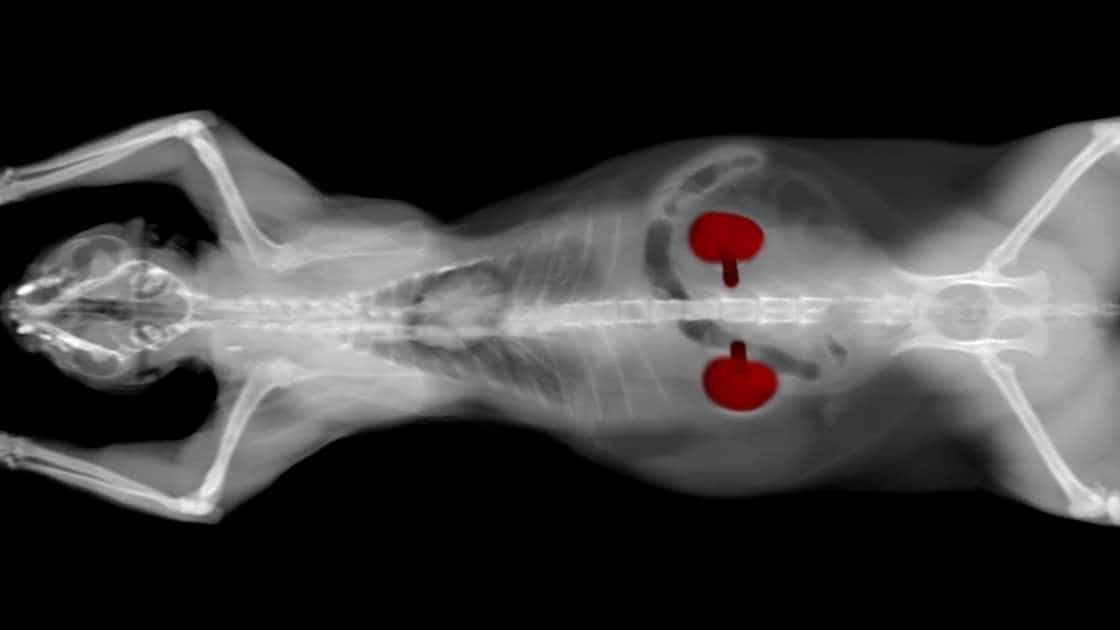

Kidney disease, also sometimes referred to as renal failure, affects around 20 to 50 percent of cats over the age of 15. Unfortunately, kidney disease is one of the most sneaky conditions, making it difficult to diagnose until its later stages. This is because kidney disease symptoms can be extremely subtle and is easily missed by the most attentive pet owner.

Kidney issues are crucial to catch and treat early; therefore, cat owners must take their furry pals to their annual vet visits to avoid this common disease. There are two types of kidney disease that can originate in cats: chronic and acute. It’s important to understand which one your four-legged friend may have in order to determine their treatment and care.

Kidney disease can develop in cats of any breed, age, or gender; therefore, it’s important to know what causes acute and chronic kidney failure.